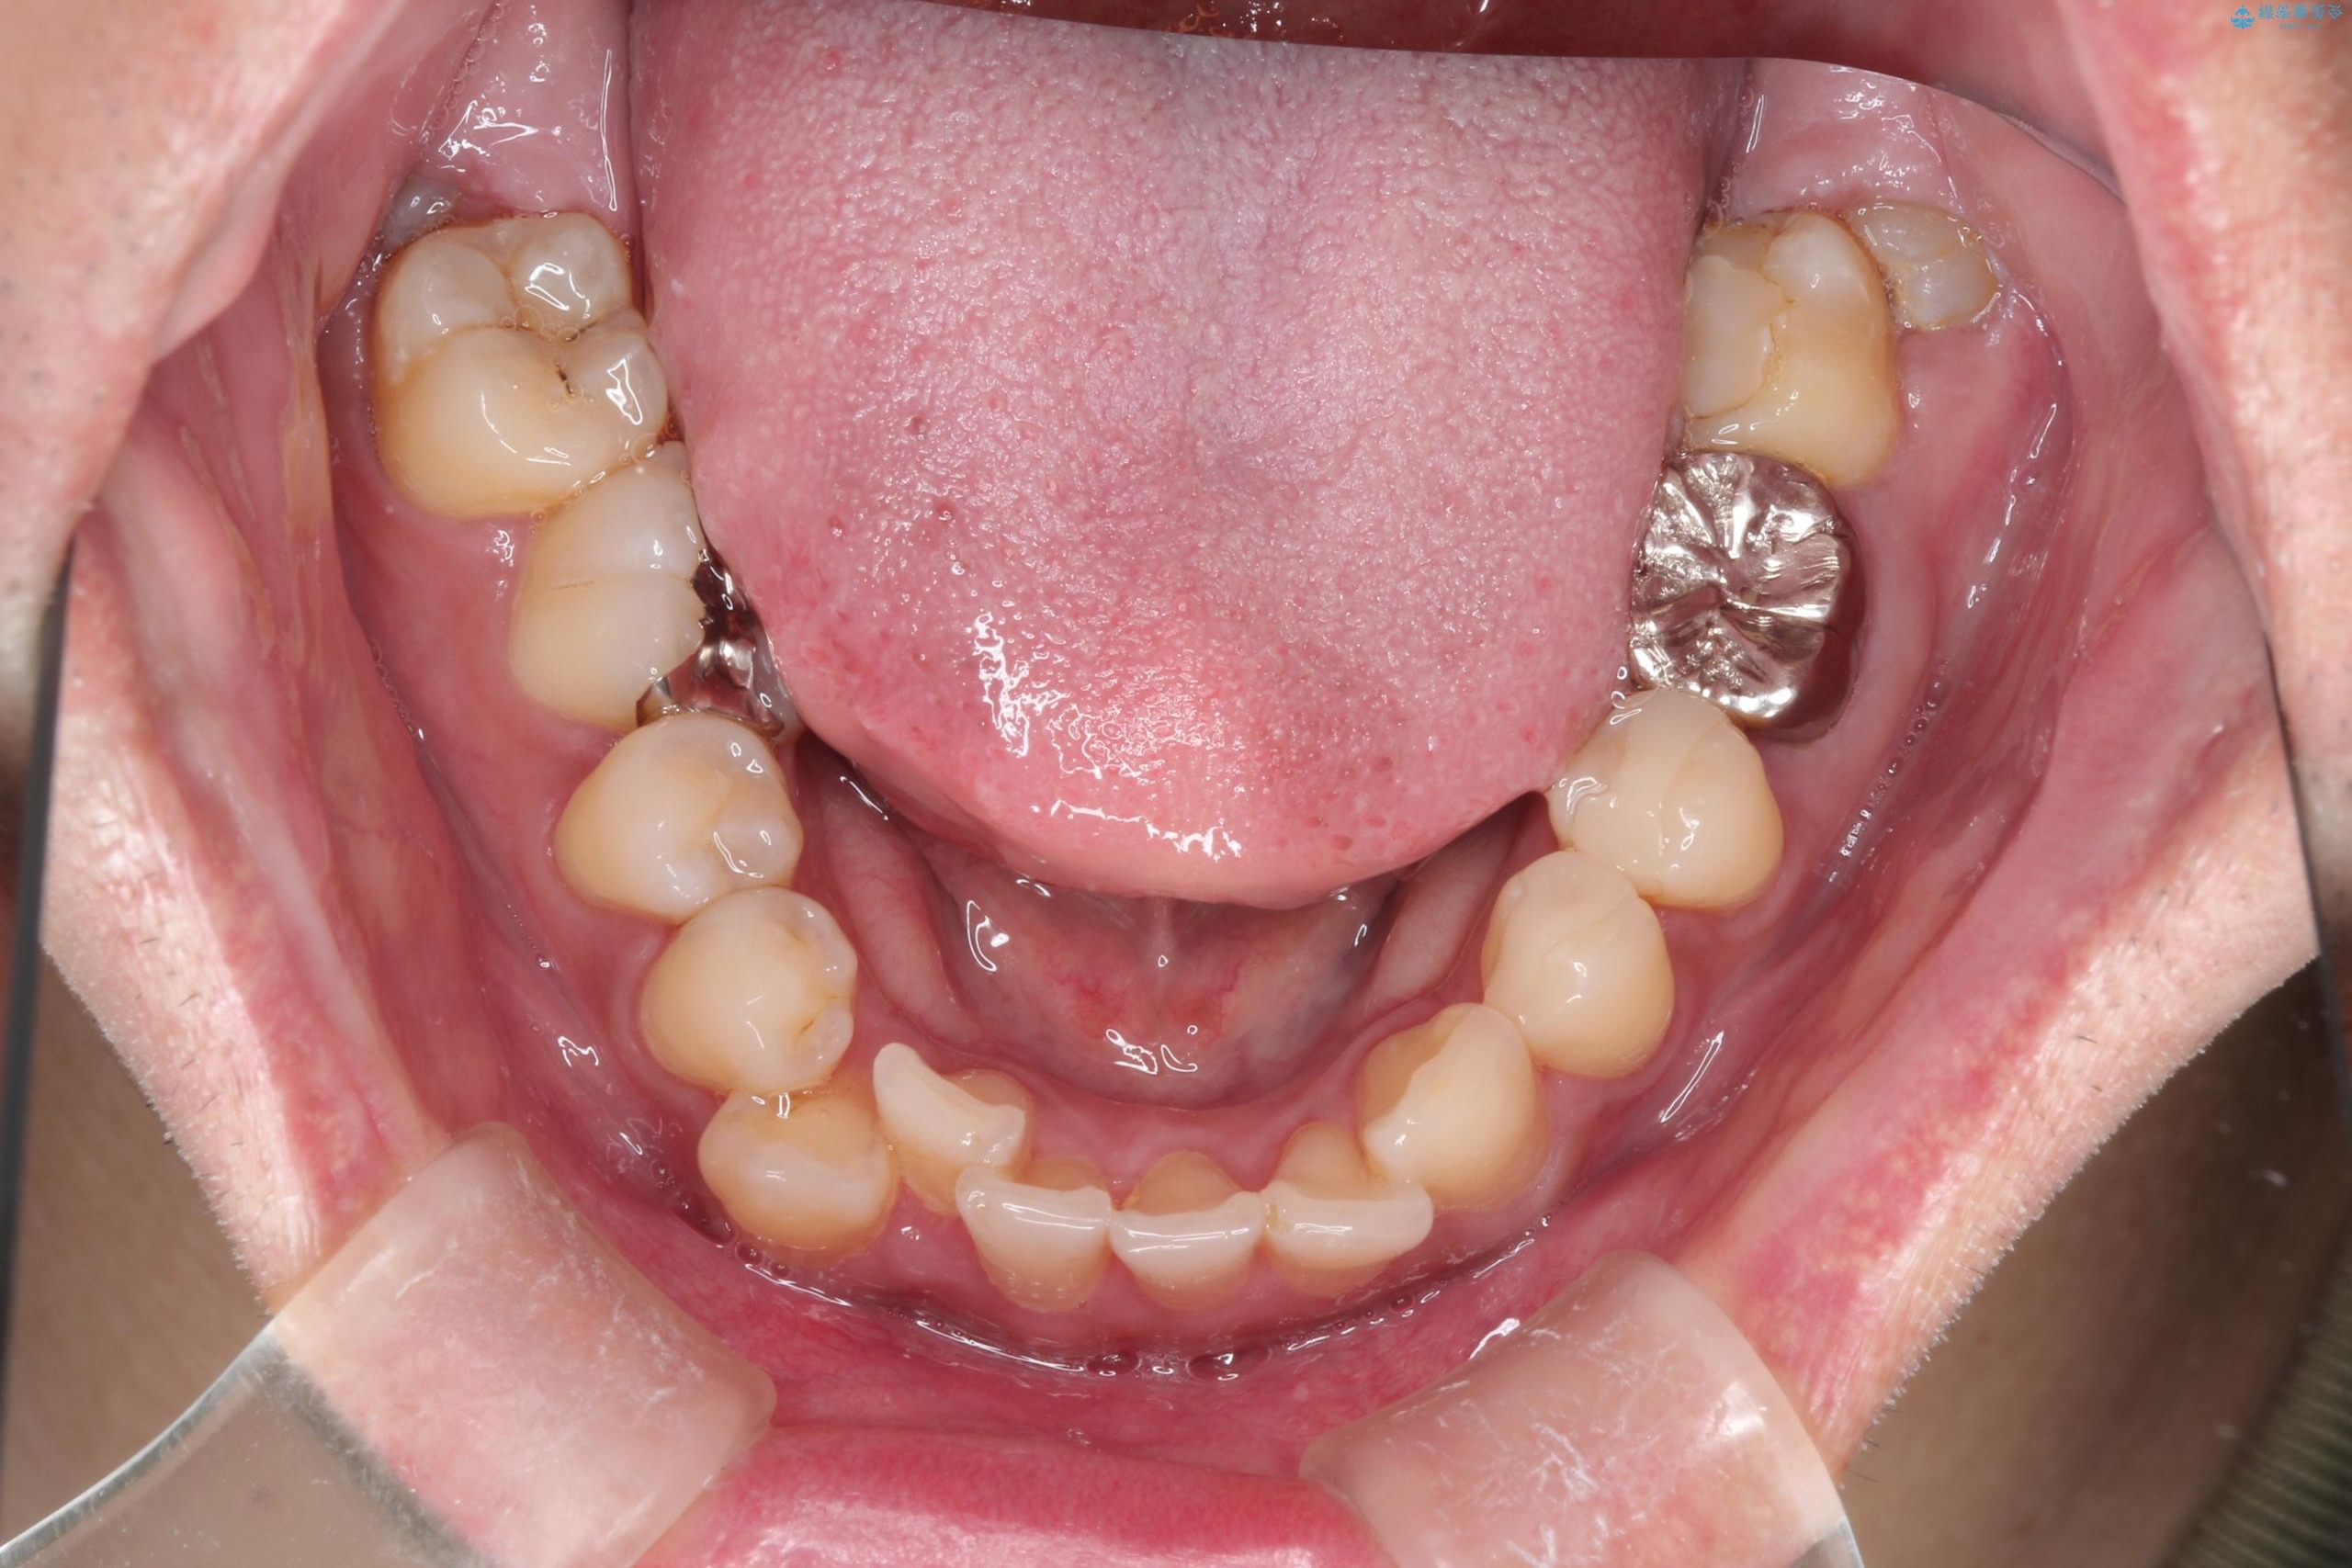

- 主訴:右上の八重歯と、下の歯の凸凹を治したい

上顎右側第一小臼歯と下顎右側第一小臼歯を抜歯しワイヤー矯正を行いました。

右側2級、左側1関係だったため、右側上下第一小臼歯を抜歯し、ワイヤー矯正を行いました。